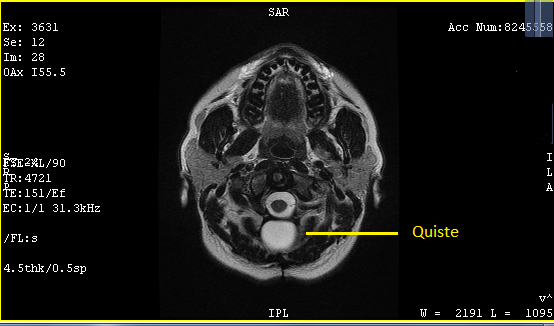

En noviembre 2019 6.8 x 3.5 x 1.6 cm y 20 centímetros cúbicos.

En enero del 2020 5.5 x 2.4 x 1 cm y 7.6 centímetros cúbicos

27 Julio 2020 4.1 x 3.0 x 1.6 cm y 11.04 centímetros cúbicos y un trayecto fistuloso de 0.7 cm.

Siguiendo la curva de disminución el quiste debió ser mínimo, pero aumento 4 centímetros cúbicos, no quiso ni abrir el sobre con los resultados, porque ya los había visto, se limito a decirme "Eso no puede ser posible, si fuera cierto no te sentirías ni te verías bien", "Seguramente quién lo realizó no lo comparó con los estudios previos o no supieron cómo hacerlo" "Doctor me lo hice aquí, no creo que se hayan equivocado" "¡Pues no!, yo no puedo tomar como válido este estudio así que necesito que te hagas una resonancia de cráneo"

El 6 de agosto regresé con los resultados de la resonancia, análisis de sangre y orina, esta vez yo tuve los resultados primero, así que al verlo lo primero que dije fue "¿Qué pasa doctor que mi cuerpo sigue rechazando el parche?", la resonancia confirmó lo mismo el quiste media 4.2 x 1.7 x 2.9 cm y 10 centímetros cúbicos y la fistula 4.8 mm y el remanente del tumor es de 15.1 mm, en contraste con en el ultrasonido 4.1 x 3.0 x 1.6 cm y 11.04 centímetros cúbicos y la fistula 0.7 cm.